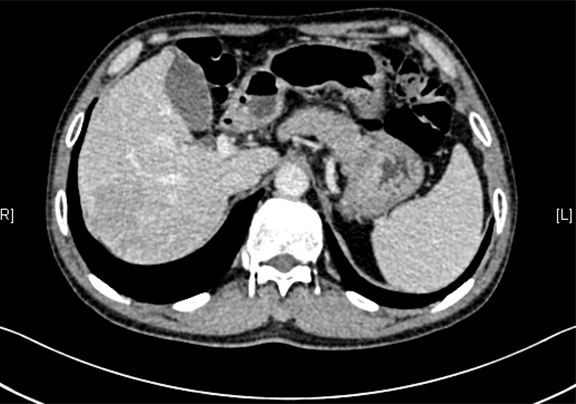

下腹部增强CT示:考虑肝右后叶肝Ca可能性大。肝顶异常强化灶,不除外不典型增生结节(DN)并癌变。肝硬化、脾大。

将0.625mm双源薄层CT资料的静脉期和动脉期Dicom格式文件导入海信CAS系统。

通过调节窗宽窗位调整CT序号,对肿瘤,肝实质,胆囊,下腔静脉,肿瘤,肝动脉、门静脉及肝静脉等进行三维重建;系统自动计算肿瘤体积和肝脏体积。

术前CT检查:

动脉期

静脉期

平衡期